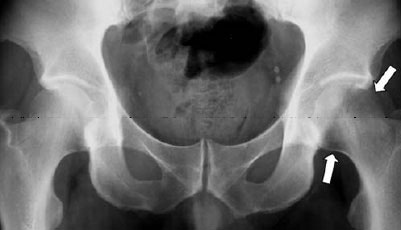

- X-rays. In the early course of the disease (the first 6 weeks), x-ray images may show a subtle decrease in the bone density of the femoral head, but this may be hard to see. Several months later, x-rays may show a dramatic loss of bone density with a near complete disappearance of the femoral head. This temporary loss of bone density is why the disease is termed "transient osteoporosis of the hip."

This x-ray of the pelvis shows early changes in bone density in the affected hip (white arrows).

Reproduced with permission from Korompilias AV, Karantanas AH, Lykissas MG, Beris AE: Transient osteoporosis. J Am Acad Orthop Surg 2008; 16:480-489.